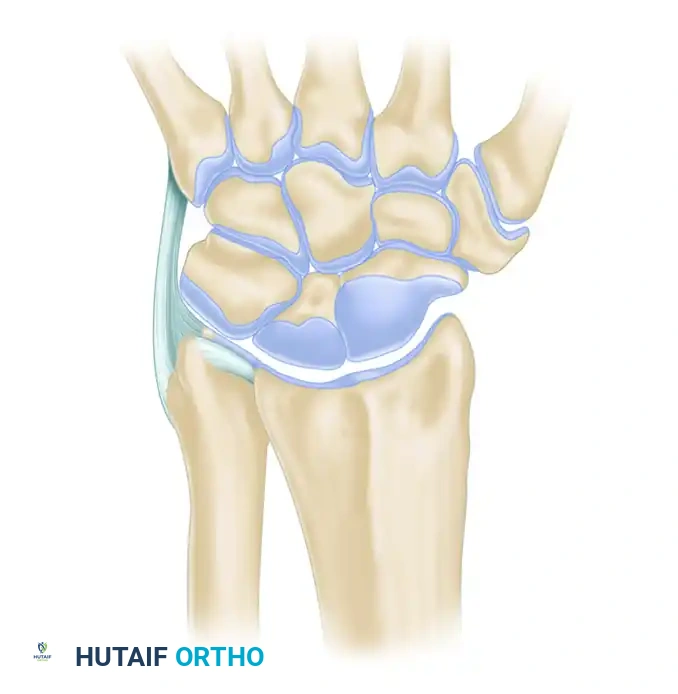

Triangular Fibrocartilage Complex (TFCC)

The TFCC is the primary stabilizer of the DRUJ and the ulnar carpus. It separates the hyaline cartilage-covered ulnar head from the ulnar styloid and carpus.

Key Components of the TFCC:

* Articular Disc: Central avascular portion, primarily load-bearing.

* Radioulnar Ligaments (Dorsal and Volar): Primary stabilizers of the DRUJ during pronation and supination.

* Ulnar Collateral Ligament (UCL): Provides ulnar-sided capsular support.

* Meniscal Homologue: Fibrous tissue connecting the disc to the triquetrum.

* Extensor Carpi Ulnaris (ECU) Subsheath: Dynamic stabilizer.

* Ulnolunate and Ulnotriquetral Ligaments: Prevent volar subluxation of the ulnar carpus.

Surgical Warning: The central portion of the TFCC is avascular and incapable of primary healing. Tears in this region require debridement. The peripheral 10-20% is vascularized and amenable to primary surgical repair.